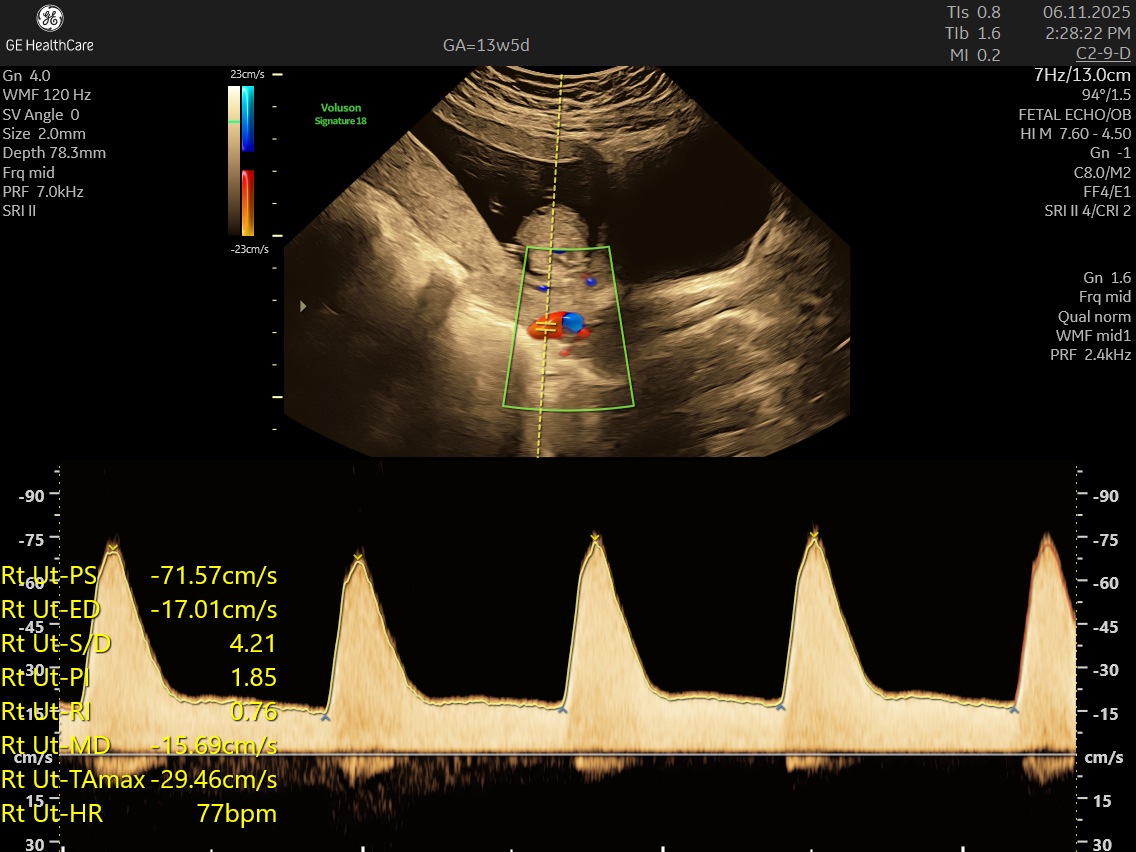

Pre-eclampsia screening is a first-trimester test done around 11–14 weeks to check your risk of developing pre-eclampsia — a pregnancy complication where your blood pressure rises and affects your baby’s growth and the placenta’s health. Pre-eclampsia screening is an early warning system to catch the risk before the problem even starts.

This is when the placenta is developing and biomarkers (like PLGF) give the clearest signals.